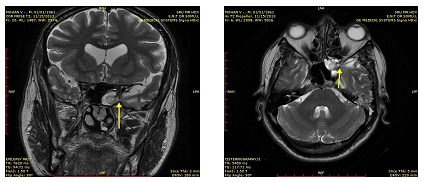

A 53year old gentleman came to the OPD with chief complaints of clear watery discharge from the left nasal cavity for the past one and a half months. Examination showed clear watery discharge when the patient bent forward indicative of cerebrospinal fluid. Diagnostic nasal endoscopy showed an active CSF leak from the sphenoid recess. CT of paranasal sinuses showed mucosal thickening in the left side of the sphenoid sinus and left posterior ethmoidal sinus with obstruction of sphenoethmoidal recess (Figure 1). MRI Cisternography showed evidence of bony defect in the left lateral wall of the sphenoid sinus measuring 9 x 10mm (CC x AP) with hernia ion of the small portion of the medial left temporal lobe with dura & CSF- suggestive of left medial temporal lobe encephalocele (Figure 2 & 3).

Figure 2&3 MRI Cisternography pictures showing defect in the left side of the sphenoid sinus with hernia ion of small portion of the left temporal lobe with dura & CSF.